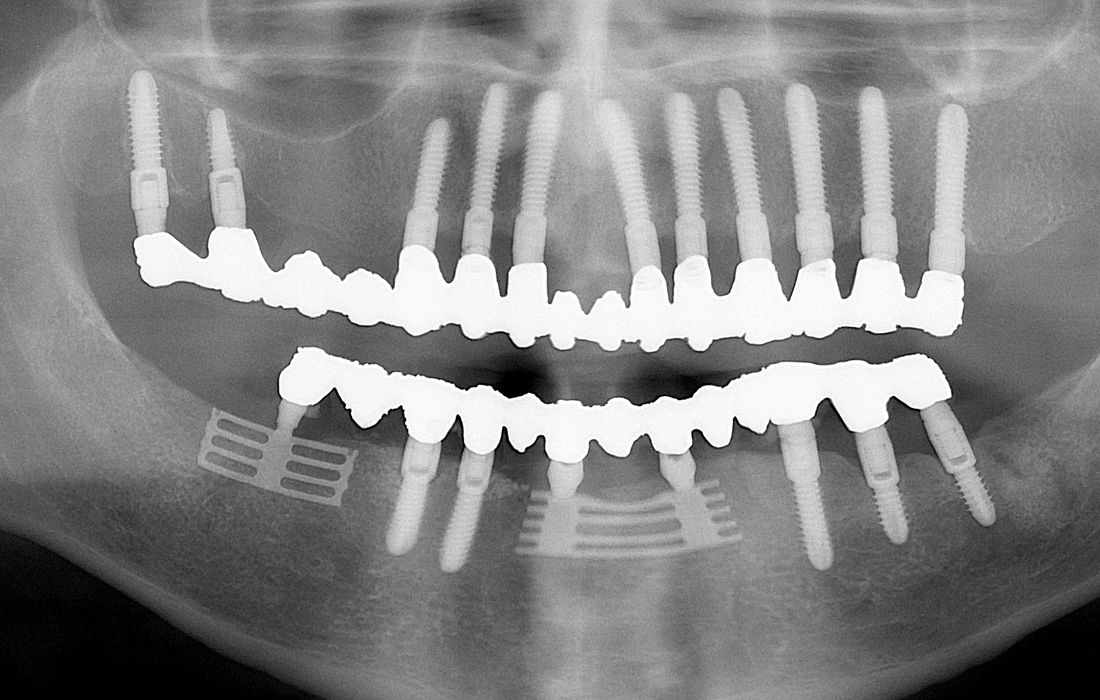

This patient presented with terminal dentition due to extensive caries and advanced periodontal disease. After removing the patient’s remaining teeth, Hahn Tapered Implants were placed during the same appointment to support a fixed restoration, and healing abutments were delivered. Four months later, a monolithic zirconia full-arch restoration was delivered, providing the patient with renewed function, esthetics and quality of life.

Replace Select and Hahn Tapered Implant x-ray

The patient, whom Dr. Hahn has been treating for several decades, has received implant restorations on many occasions to replace teeth lost due to fracture or decay. Placing implants is one of the best means of patient retention, as many people value the ability to receive the full circle of care from their general dentist. Note the various implant systems, all of which Dr. Hahn designed based on his clinical experience and observations over the last 50 years.